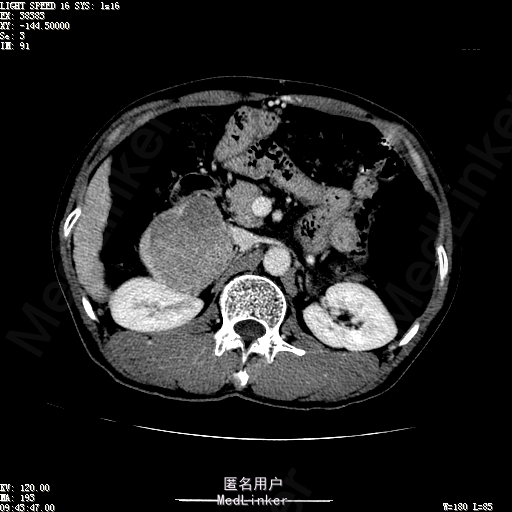

查体:体温36.4℃,脉搏76次/分,呼吸18次/分,血压110/70mmHg。神志清晰,发育正常,营养中等,体位自如,表情安静,慢性病容,检查合作。皮肤粘膜颜色正常,无瘀点、紫癜,有肝掌,无蜘蛛痣,无水肿,毛发的生长与分布正常。浅表淋巴结浅表淋巴结未触及肿大。无巩膜黄染,结膜正常。口唇红润,粘膜正常,舌正常,牙龈正常,扁桃体无肿大,无咽部充血。颈部外形对称,颈静脉正常,肝颈静脉回流征阴性,气管居中。甲状腺正常,无颈部血管杂音。胸部形态正常,呼吸运动平稳规律,无呼吸困难,肋间隙正常。触诊语颤正常,无胸膜摩擦感,肺下界位于右锁骨中线第六肋间。呼吸音正常,未闻及干湿啰音,无胸膜摩擦音。无心前区隆起,心尖搏动正常,心率:76次/分,心律齐,心音正常,无杂音,无心包摩擦音。无大动脉及周围血管征,无奇脉及交替脉,无水冲脉,无枪击音,腹型对称,无腹壁静脉曲张,未见胃肠型及蠕动波,无瘢痕,脐部正常。无压痛,无反跳痛,无腹肌紧张,无腹部包块。肝未触及,Murphy征阴性,脾未触及,肾未触及,无移动性浊音。无肝区叩击痛,无肾区叩击痛,无脾区叩击痛。肠鸣音正常4次/分,无气过水声。外阴及肛门:未查。四肢正常,关节正常,无下肢水肿,无下肢静脉曲张,无杵状指趾。 辅助检查:彩超:肝表面欠光滑,肝内占位5.2*5厘米 ct如下图

诊断:乙肝肝硬化 代偿期 原发性肝癌。 患者病史明确,目前化验转氨酶轻度升高,说明有活动性肝损伤,白蛋白降低提示肝脏合成代谢功能下降,AFP从一年前至今逐渐升高,提示活性肿瘤细胞增多。CT所见明确诊断肝癌,并有周围卫星灶,应近期行TACE治疗。 处置:DSA下肝动脉造影及TACE 手术简要经过:患者平卧位,术区皮肤消毒,铺手术巾,2%利多卡因局麻后,Seldinger法穿刺右股动脉,入血管鞘,5F猪尾管腹主动脉造影,超滑导丝yidao5F RH管腹腔干、肠系膜上动脉、左肾动脉分别造影,腹腔干造影时,见肝右叶7-8处小结节样肿瘤染色,未见外凸生长较大病灶染色。微导管超选肝右动脉注入三氧化二砷碘油混悬液10毫升,横结肠遮挡部位见较大病灶有伞状碘油沉积。复查造影未在见肿瘤染色,拔出导管和血管鞘,穿刺处压迫止血,加压包扎。术毕。

患者术后8天来,无不适,无发热,无腹痛和腹胀,无恶心呕吐,食欲睡眠好,尿便正常。 查体:神志清,巩膜无黄染,心肺听诊无异常,腹软,无压痛,肝脾肋下未触及,移动性浊音阴性,双下肢无浮肿。 复查化验结果:丙氨酸氨基转移酶 116 U/L、天门冬氨酸氨基转移酶 41 U/L、胆碱酯酶 1995 U/L↓、总蛋白 56.3 g/L、白蛋白 25.9 g/L。白细胞计数 5.8 10^9/L、红细胞计数 3.18 10^12/L、血小板计数 175.0 10^9/L、*血红蛋白 83 g/L、血小板分布宽度 15.7 、血小板压积 0.175 %、*红细胞压积 24.6 %、平均红细胞血红蛋白 26.1 pg、平均红细胞血红蛋白浓度 337.0 g/L、平均红细胞体积 77.5 fL、平均血小板体积 10.0 fL、嗜碱性粒细胞百分比 0.4 %、嗜碱性粒细胞数量 0.02 10^9/L、中性粒细胞百分比 70.4 %、中性粒细胞数量 4.10 10^9/L、嗜酸性粒细百分比 2.1 %、嗜酸性粒细胞数量 0.12 10^9/L、单核细胞百分比 12.2 %、单核细胞计数 0.7 10^9/L、淋巴细胞数量百分比 14.9 %、淋巴细胞计数 0.9 10^9/L。甲胎蛋白 23564.00 ng/mL 患者术后第8天开始行FOLFOX6化疗。CT上可见明显碘油沉积,术后甲胎蛋白下降治疗有效。嘱患者术后必须定期复查